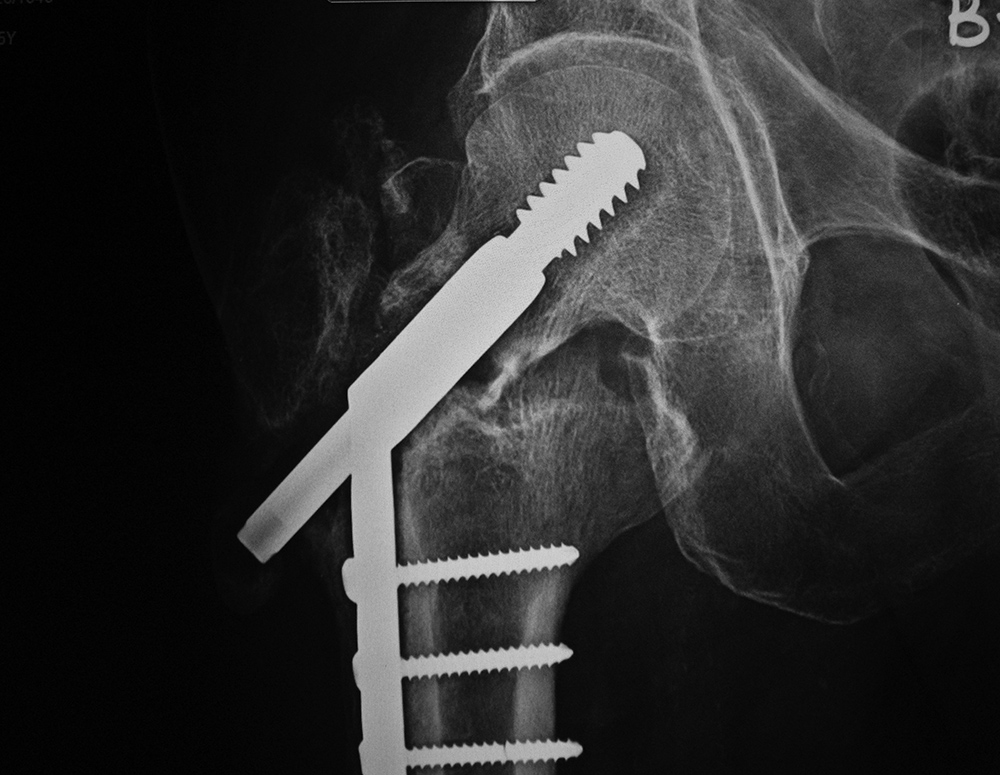

Intraoperative fixation of an intertrochanteric fracture demonstrates a cephalomedullary device with the tip of the cephalic screw positioned too short and very inferior in the neck (very large tip-apex distance). |

Subsequent fracture fixation failure observed as the head and neck segment of the femur flexed 90 degrees with cut-out of the screw approaching the hip joint. |